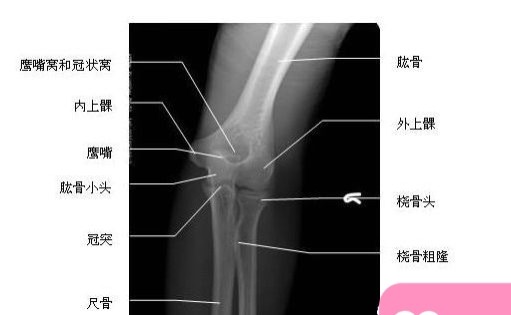

肘关节正位图片上大致可以看到肱骨、尺骨、桡骨、尺骨鹰嘴、内上髁、外上髁及桡骨小头。

肘关节侧位片上大致可以看到肘关节、肱骨、尺骨、桡骨、尺骨鹰嘴、桡骨小头、肱骨小头。